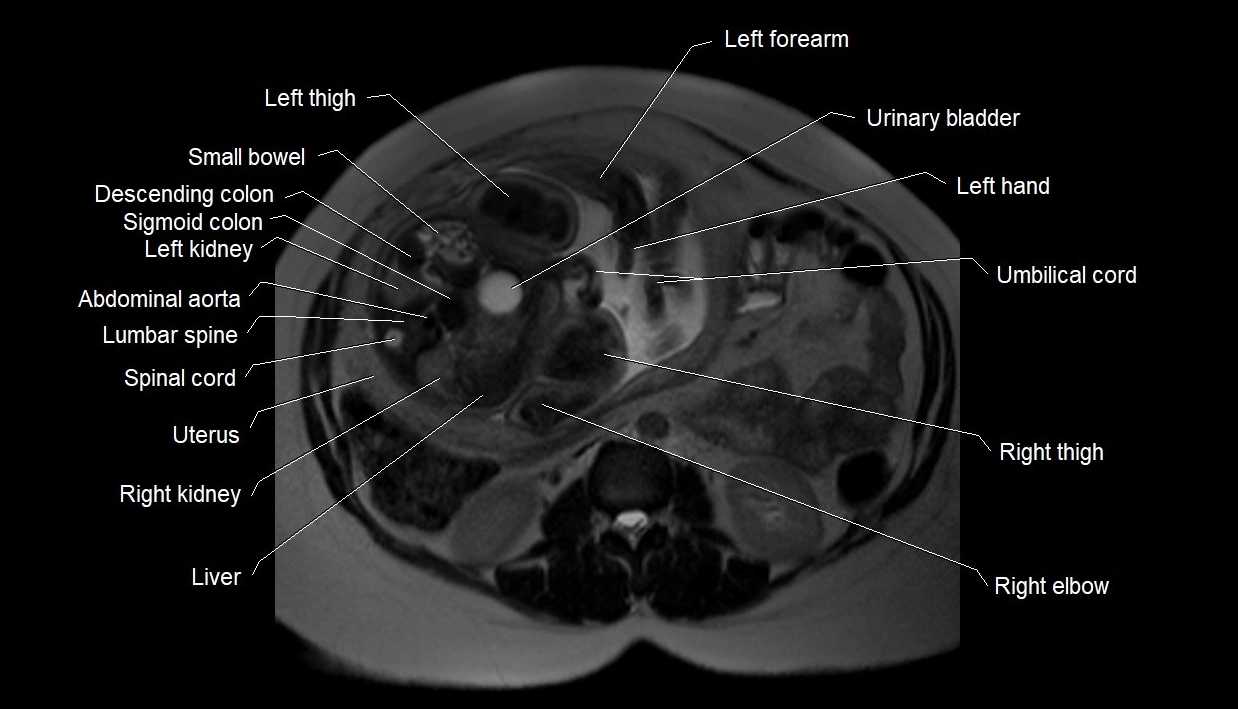

MRI Appearance

T2 HASTE (T2 GRE):

• Amniotic fluid shows very bright hyperintense signal

• Provides natural contrast against fetus and placenta

• Small particles (vernix) may appear as scattered hypointense foci within bright fluid

T1 GRE:

• Amniotic fluid shows low signal intensity (dark)

• Hemorrhage, infection, or proteinaceous content may cause focal or diffuse high signal intensity